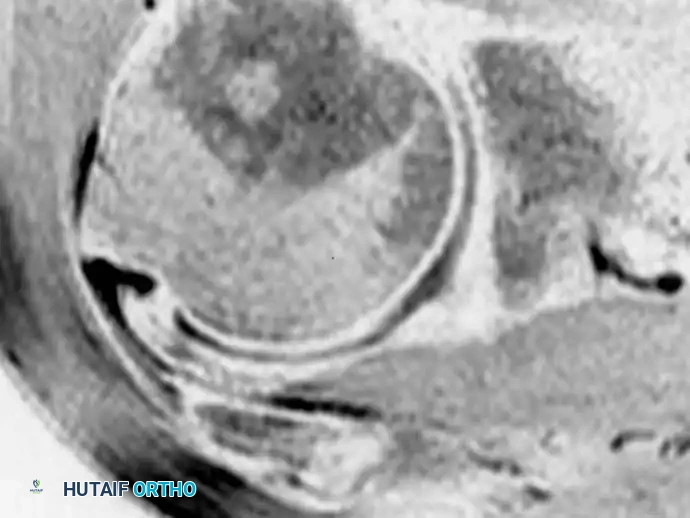

توضح هذه الصورة مقطعا إكليليا مائلا للكتف بدون تقنية قمع الدهون، حيث يصعب التمييز بوضوح بين الوتر الطبيعي والأنسجة المتمزقة، مما يجعل تحديد حواف التمزق بدقة أمرا وتحديا للطبيب.